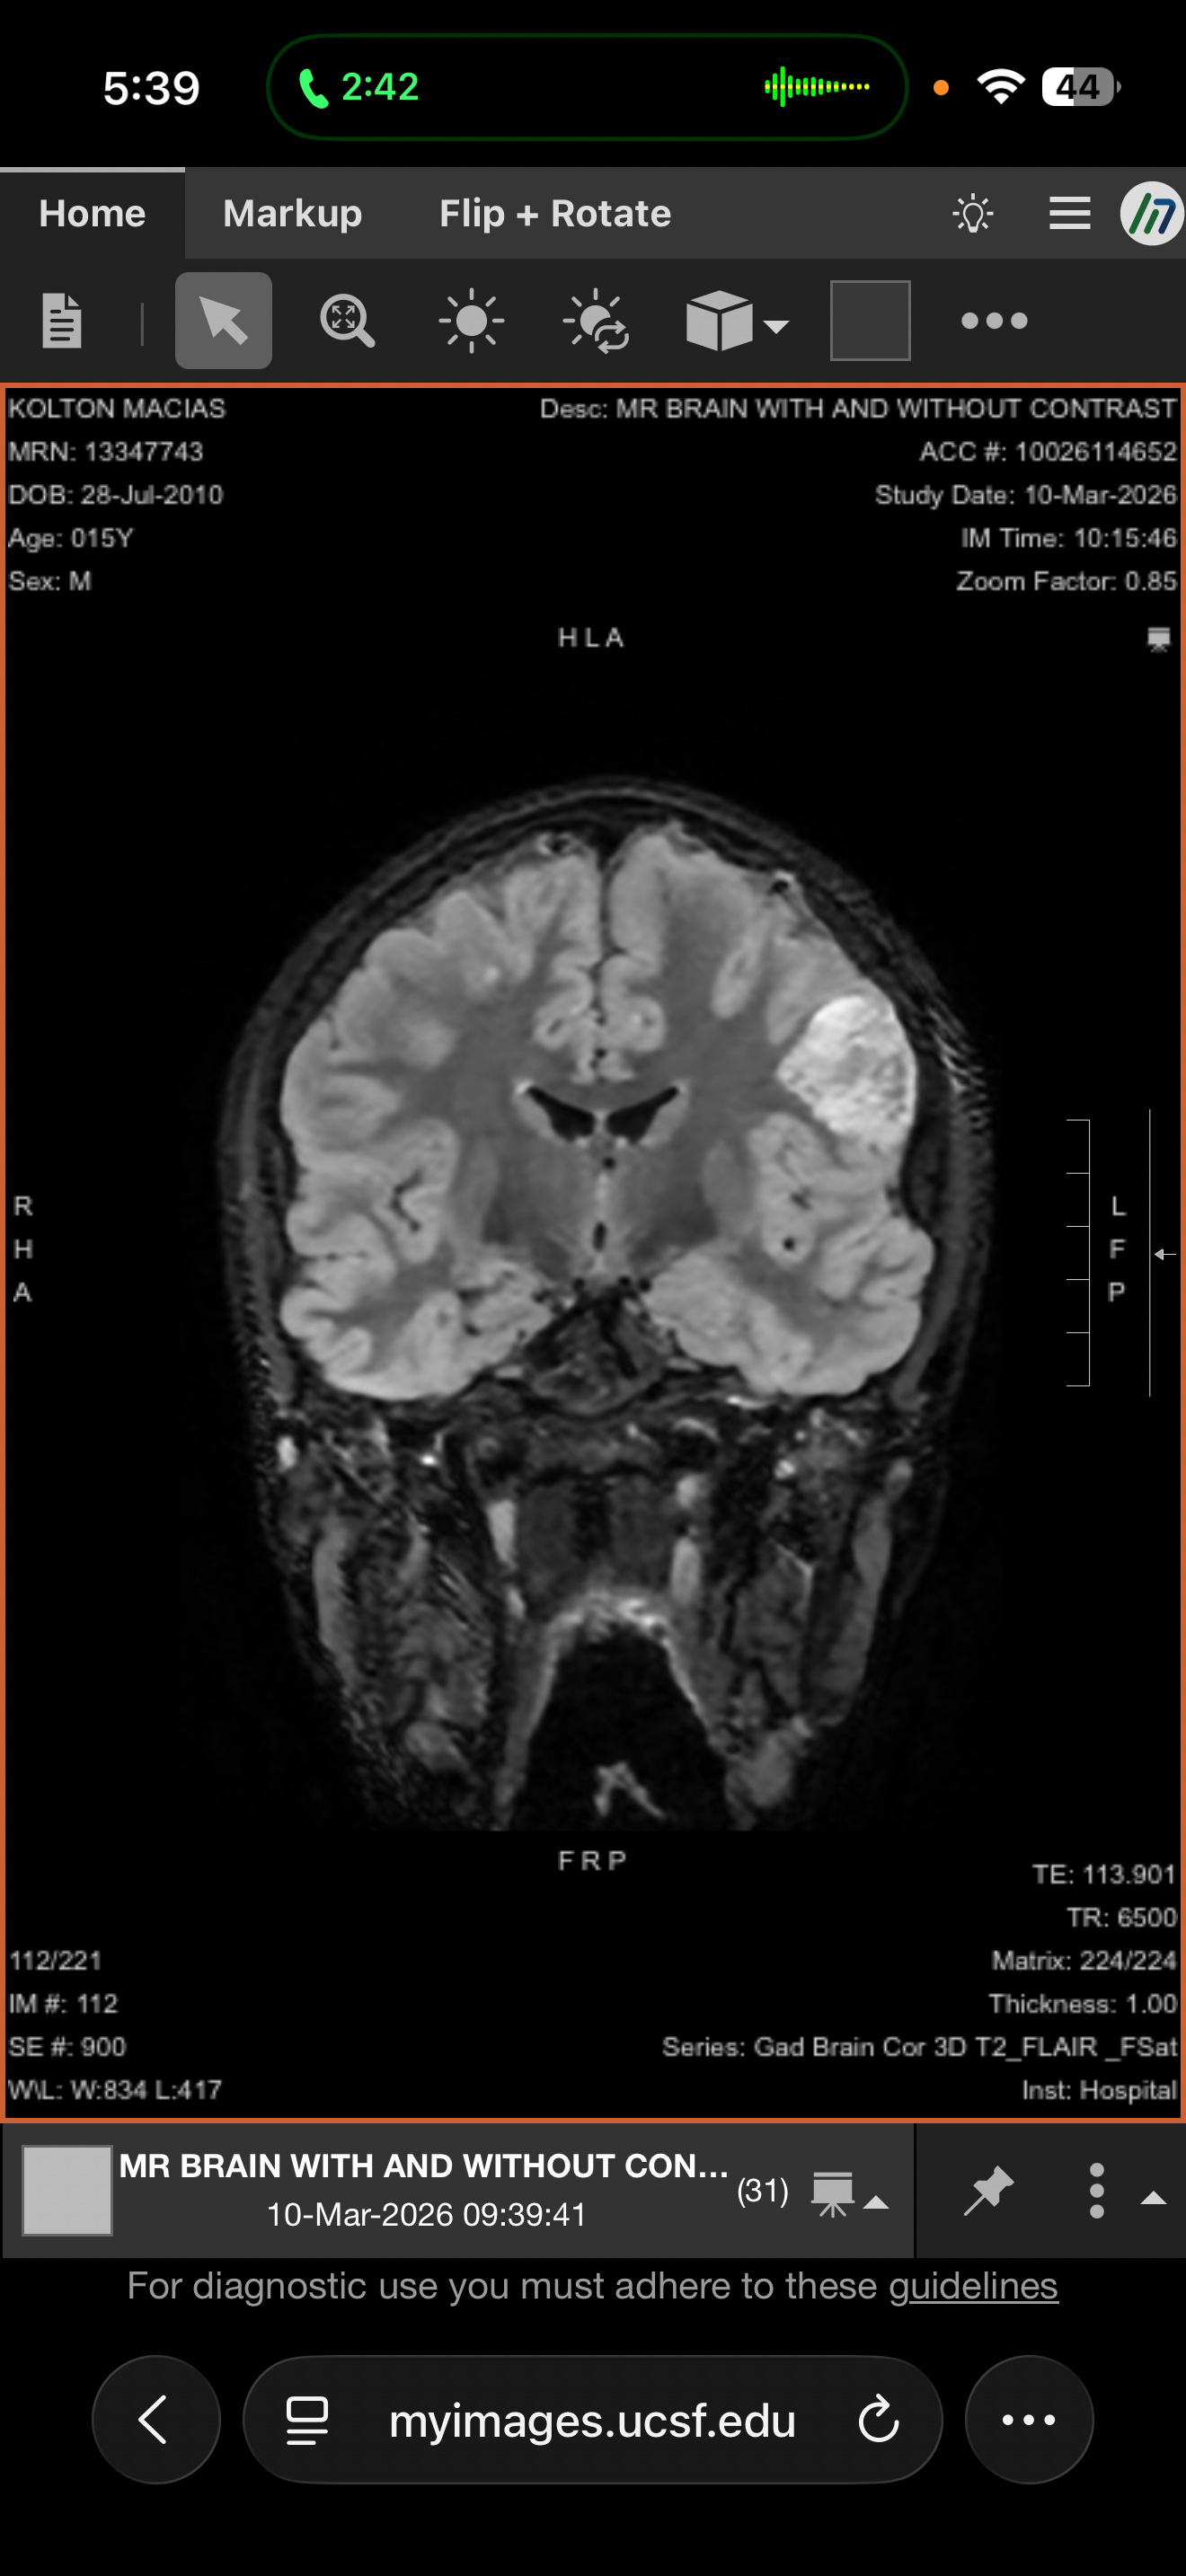

Our hearts are heavy as we share that Kolton has recently been diagnosed with multiple brain tumors. After urgent evaluations, doctors discovered four tumors, including one located in the cerebellum. At this time, Kolton’s medical team is moving forward with a biopsy and laser ablation procedure to treat one of the tumors. The remaining tumors are expected to be managed with oral medications and ongoing treatment. This journey will require frequent monitoring, including MRIs every 3 months, and close follow-up with specialists.